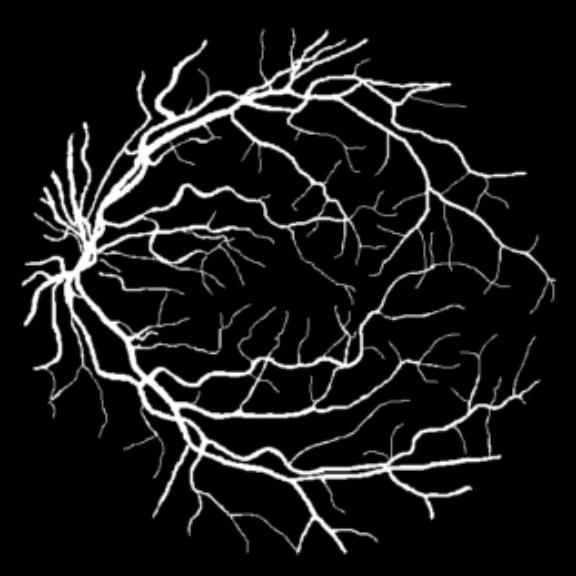

All three datasets are processed by subtracting the mean and normalizing according to the standard deviation. We use Adam optimizer, set the initial learning rate to 0.001 which is reduced by ten times if the training set loss does not drop during 10 consecutive epochs. We augment data using rotation, crop, flip, shift, change in contrast, brightness and hue. We set batch size to 4 for Skin Dataset and 32 for DRIVE and CHASE_DB1 whose patch size is relatively smaller. For each model we train 50 epochs and the result is shown in Table 1. Models with MixModule have better performance than those not and the best performance in each metric all comes from MixModule-based models. We also show some outputs of the networks in Figure 4.